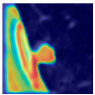

To assess clinical applicability, the model was validated on MEF-PN35—a real-world dataset comprising 804 CT slices from 35 patients with diverse nodule morphologies. Performance was evaluated using the Dice score, sensitivity, specificity, and Miss Rate. Additionally, Grad-CAM visualizations were employed to interpret attention consistency, offering qualitative insights into the model’s focus on lesion regions in realistic clinical scenarios.

Following the summary in Table 11, we present detailed visual comparisons for selected representative cases, each corresponding to a specific segmentation challenge. These cases are consistently labeled using the Challenge ID (CID) codes defined in Table 9 to facilitate cross-referencing between the summary and the case illustrations. Each table reports segmentation results across three loss configurations (Sobel, Laplacian, and Hausdorff) using five columns. Loss indicates the boundary loss formulation applied in each case, where Dice loss is combined with a boundary term computed using Sobel, Laplacian, or Hausdorff operators. The Segmentation Result column shows four images side by side: the input CT patch, the manual ground truth, the model prediction, and a color-coded difference map between ground truth and prediction. In this map, green indicates true positives, blue represents true negatives, red corresponds to false positives, and yellow denotes false negatives. The final column, Attention Map, presents Grad-CAM visualizations derived from one of the Adaptive Attention Fusion (AAF) layers in the encoder path. These maps illustrate the spatial focus of the model, with red/yellow regions indicating strong attention and lighter or neutral tones indicating lower activation. All six cases are presented in detail in Table 11, Table 12 and Table 13, providing a comprehensive qualitative analysis of how each loss configuration performs under specific segmentation challenges observed in real clinical data.